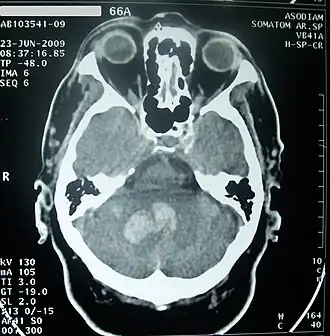

![]() TAC de cráneo mostrando hemorragia intracerebral profunda por sangrado en el cerebelo (zona grisácea), aproximadamente 30 horas desde su inicio. | ||